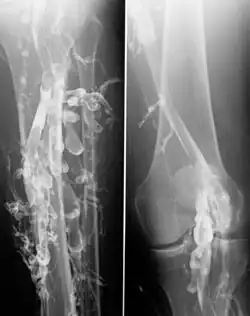

![]() Flebografía en un paciente con trombosis venosa profunda. | ||

La venografía (también llamada flebografía o flebografía ascendente) es un procedimiento en el que se toma una radiografía de las venas, un venograma, después de inyectar un colorante especial en la médula ósea o las venas. El tinte se debe inyectar constantemente a través de un catéter, por lo que es un procedimiento invasivo. Normalmente, el catéter se inserta por la ingle y se mueve al sitio apropiado navegando a través del sistema vascular.

La venografía de contraste es el estándar principal para diferenciar los métodos de diagnóstico por imágenes para la trombosis venosa profunda; aunque, debido a su costo, invasividad y otras limitaciones, esta prueba rara vez se realiza.[1]